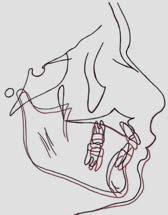

En la radiografía lateral de cráneo ( Figura 6 ) se ve la línea estética de Rickets, que el labio superior se encuentra a +0.5 mm y el inferior a -2 mm. En las mediciones cefalométricas más importantes en la figura 11 un ANB de 5º, GoGn-SN de 33º y FMA de 21º crecimiento normodivergente y Witts de -1 mm. A los criterios dentales encontramos

1-PLT de 129º e IMPA 99º proinclinación de incisivos tanto superiores como inferiores. En la radiografía panorámica (Figura 7), la presencia de 32 órganos dentarios, con terceros molares inferiores aún sin erupcionar y terceros molares superiores

Secuencia de radiografías laterales de cráneo (Figura 15) vemos que el ANB disminuyo 1º de inicio a fin clase I con tendencia a clase II esquelética a final. Reducción de Witts 0.5 mm final, crecimiento normodivergente. Mandíbula más pequeña que el maxilar, cambio por el avance mandibular.

Referente a los criteriso dentales, el incisivo maxilar respecto a su base ósea tuvo una importante retroinclinación, inció en 129º y finalizó en 111º, en cuanto al incisivo inferior, este se proinclinó 1º, de 99º a 100º.

Sobreimposiciones incio-final sobre componente craneofacial figura 20 paciente adulto sin crecimiento, con descenso y avance mandibular con bite ramps, modificación en el perfil facial a nivel de labio inferior y proyección del mentón. Sobre maxilar (Figura 21) extrusión y ligera distalización del primer molar superior y retroinclinación y ligera extrusión del incisivo superior pasa de 1-PLT de 129º a 111º. Sobre sínfisis figura 22 ligera extrusión y verticalización del molar inferior y proinclinación y extrusión del incisivo inferior,